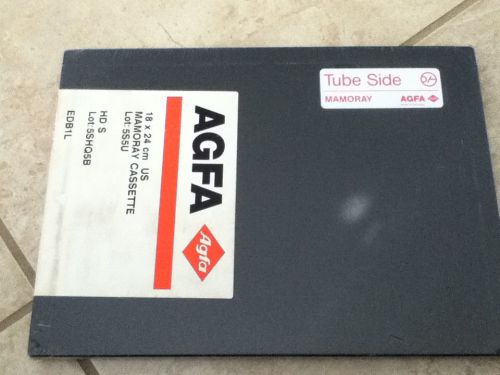

New Sealed 18 X 24 AGFA MAMORAY CASSETTE